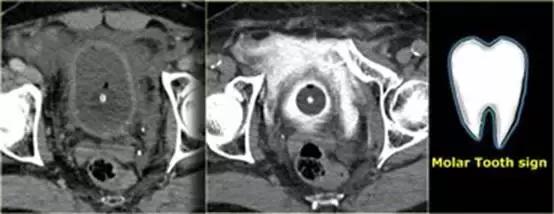

膀胱造影前后CT对比图像

膀胱中导尿管有对比剂, 膀胱直肠隐窝中也有渗出的对比剂。

‘磨牙征’ 提示腹膜外膀胱破裂。